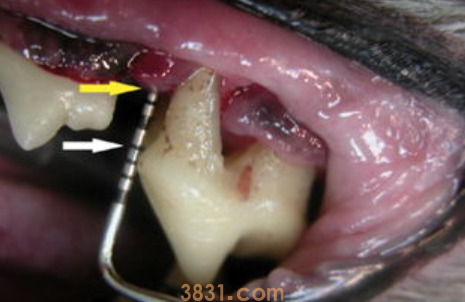

猫牙结石的形成不仅仅会可能导致口腔卫生问题,还可能会影响到严重点的全身细菌感染。

如果发现牙齿结石严重点,我建议你到正规店机构求专业的牙科治疗,比如接受冷光美白等必要的牙科手术,最终达到全部清除掉牙结石。

在不痛不痒的状态下,牙结石容易被忽视,但还没了很不舒服甚至还细菌感染后,再参与治疗则是需要一定时间压制病情,哪怕需要大量的医疗费用和心理压力。